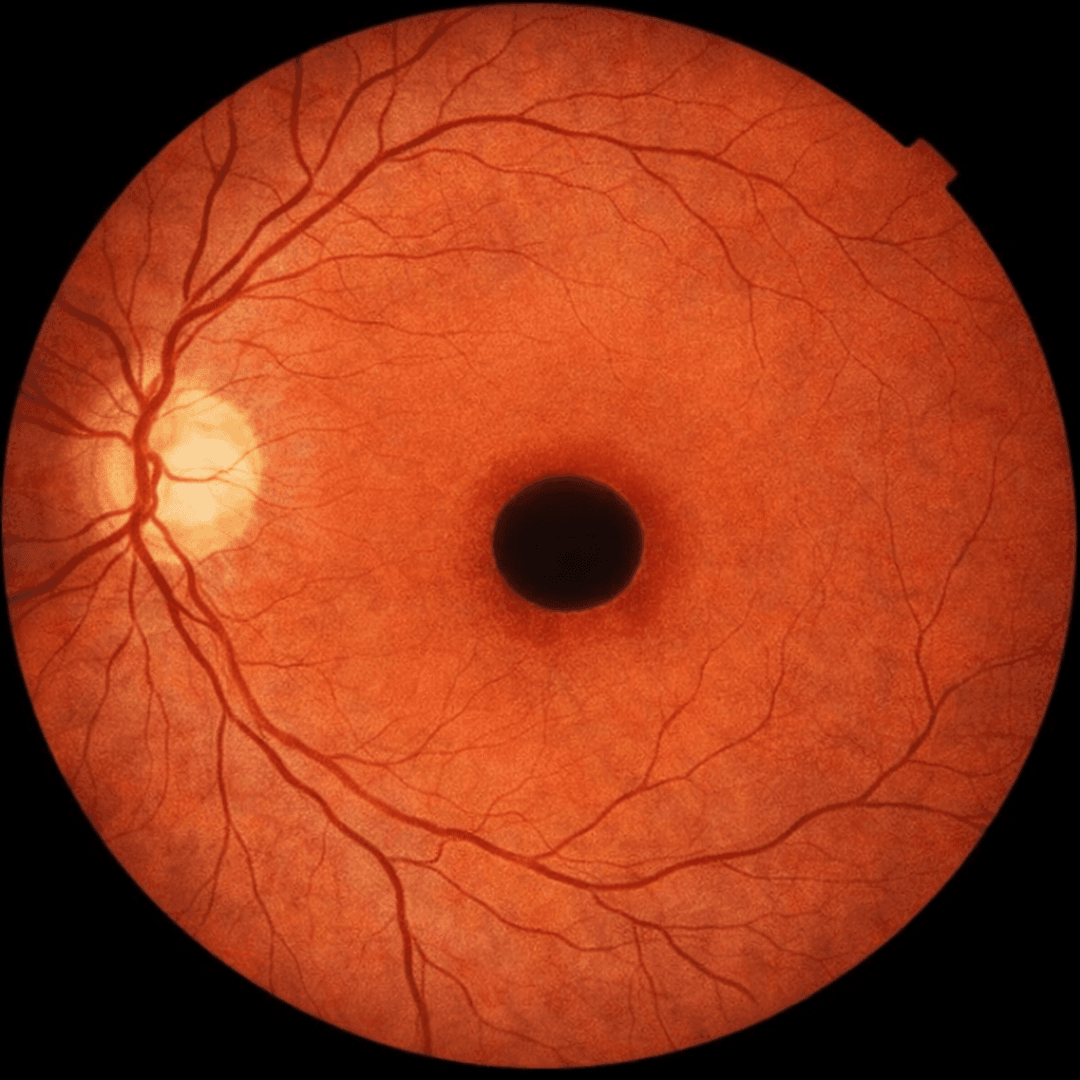

우리 눈의 필름인 망막의 중심부, '황반'에 작은 구멍이 뚫리는 질환입니다.

황반은 시력의 90% 이상을 담당하는 매우 중요한 부위로, 이곳에 구멍이 생기면 급격한 시력 저하와 함께 사물이 끊어져 보이거나 중심부가 보이지 않는 증상이 나타납니다. 주로 60세 이상에서 노화로 인해 유리체가 망막을 잡아당기면서 발생합니다.

중심 암점

보려고 하는 시야의 한가운데가 검게 가려져 보입니다.